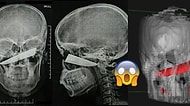

Mika Raun’un Estetik Sırrı Ortaya Çıktı: Doktoru Dünden Bugüne Yapılan İşlemleri Tek Tek Açıkladı! 12 Nisan, 18:17